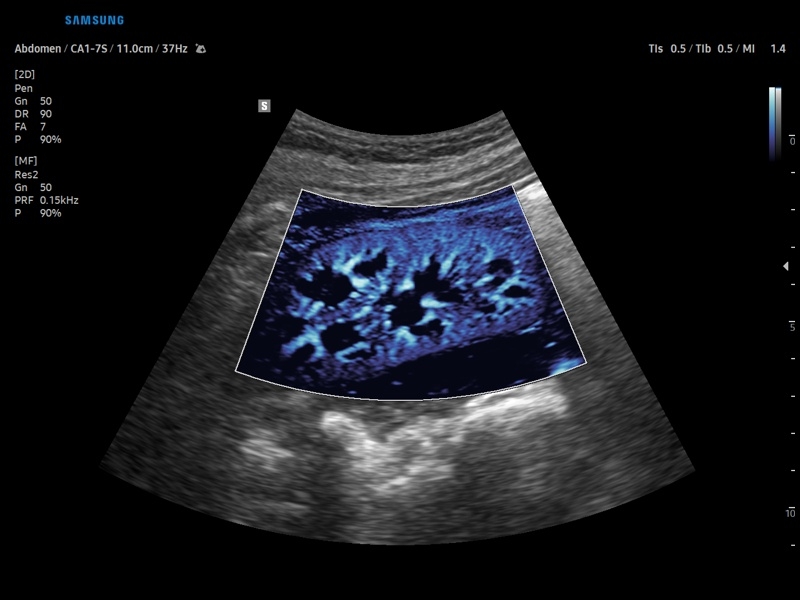

Ультразвуковой сканер V8-RUS является экспертным классом (премиальный уровень) и производится компанией Samsung Medison. Сканер V8 обеспечивает превосходное качество изображения благодаря использованию технологии Crystal Architecture™, которая включает в себя передовое аппаратное обеспечение, монокристальную технологию изготовления датчиков и сложную программную обработку ультразвуковых лучей.

• Абдоминальные исследования

• Модуль MV-Flow – программа (режим), позволяющая визуализировать кровоток в микроциркуляторном русле с высоким разрешением без использования контраста.

• Модуль LumiFlow – программа отображения кровотока с объемной графикой для лучшего понимания архитектоники сосудистого русла.

• Программа SEE Stream – режим недопплеровской визуализации кровотока в реальном масштабе времени.